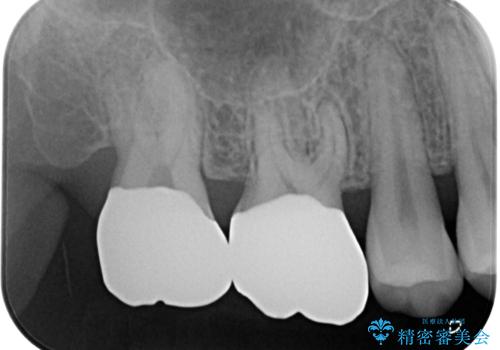

- 他院で矯正治療前後に処置を行った歯が痛むとのことで来院された患者様です。

下顎大臼歯は根管治療がされている歯が咬合時に痛みを感じ、上顎の大臼歯2歯は冷たいものがしみる状態でした。

まずはしみる上顎の歯を仮歯に置き換え、その後下顎の根管治療を行った上で、異常が認められなければオールセラミッククラウンにて補綴治療を行うこととしました。

根管治療を行った歯の周辺にある病変は数ヶ月後にレントゲン写真を撮って確認する必要があるため、今後経過観察を行っていく予定です。